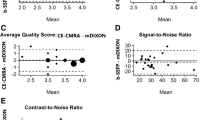

In total, image quality was assessed by each reader for 330 vessels on REACT CMRA and contrast-enhanced steady-state CMRA, respectively (overall ratings, n = 660). 30 vessels (8%) were not assessable on both CMRA methods due to pronounced susceptibility artifacts or congenital or postoperative absence of vessel structures. The overall image quality score was slightly higher for REACT CMRA compared to steady-state CMRA (3.9 ± 1.0 vs. 3.8 ± 0.9, P = 0.018) (Fig. 3A). REACT CMRA achieved a higher image quality score compared to contrast-enhanced CMRA for the ascending aorta, the inferior vena cava, and the origin of the right and left coronary artery (Table 3). A clinical example with a variant origin of a severely hypoplastic native aorta with trifurcation of the coronary arteries is shown in Fig. 4. Image quality of pulmonary arteries was comparable between REACT and steady-state CMRA (Table 3). Image quality of REACT CMRA was slightly lower for the main pulmonary artery (Table 3), which was mainly contributed to flow artifacts due to severe pulmonary insufficiency in single patients. In patients with Glenn shunt (15/36, 42%), the cavopulmonary circulation had a lower blood signal intensity compared with the systemic circulation (Fig. 5A). The image quality of pulmonary veins was intermediate with significant better ratings for contrast-enhanced CMRA (Table 3). An example of a flow artifact is presented in Fig. 5B.

Image quality and vessel diameter measurements results. A Bar plots show image quality scores for native and contrast-enhanced CMRA. B Bland–Altman plot and, C scatter plot show correlation of all vessel diameter measurements between native and contrast-enhanced CMRA. Pearson’s correlation coefficient is given. REACT relaxation-enhanced angiography without contrast

Vessel diameter measurement

Measurements of vessel diameter were performed for 285 landmarks by each reader (overall measurements, n = 570). 39 landmarks (12%) could not be assessed on both CMRA due to severe artifacts or aberrant cardiovascular anatomy. Vessel diameter measurements strongly correlated between both CMRA techniques and showed close intermethod agreement (Pearson r = 0.99; bias = 0.04 ± 0.61 mm, 95% limits of agreement: − 1.17 to 1.24 mm; Fig. 3B, C). Detailed results for vessel diameter measurements are given in Table 4. High ICCs indicated good interobserver reproducibility for the assessment of image quality (REACT: 0.87, contrast-enhanced CMRA: 0.79) and vessel diameter (REACT: 0.99, contrast-enhanced CMRA: 0.99) (Table 5).